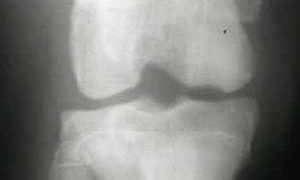

膝関節炎(inflammation of the stifle joint, gonitis) ~ 原因・症状・治療法

膝関節は大腿骨と下腿骨(脛骨と腓骨)とのなす関節ですが、前面やや上方には膝蓋骨が強固な靭帯によって結着し、大腿脛関節femoro-tibial jointおよび大腿膝蓋関節(股膝蓋関節)femoro-patellar jointを形成します...